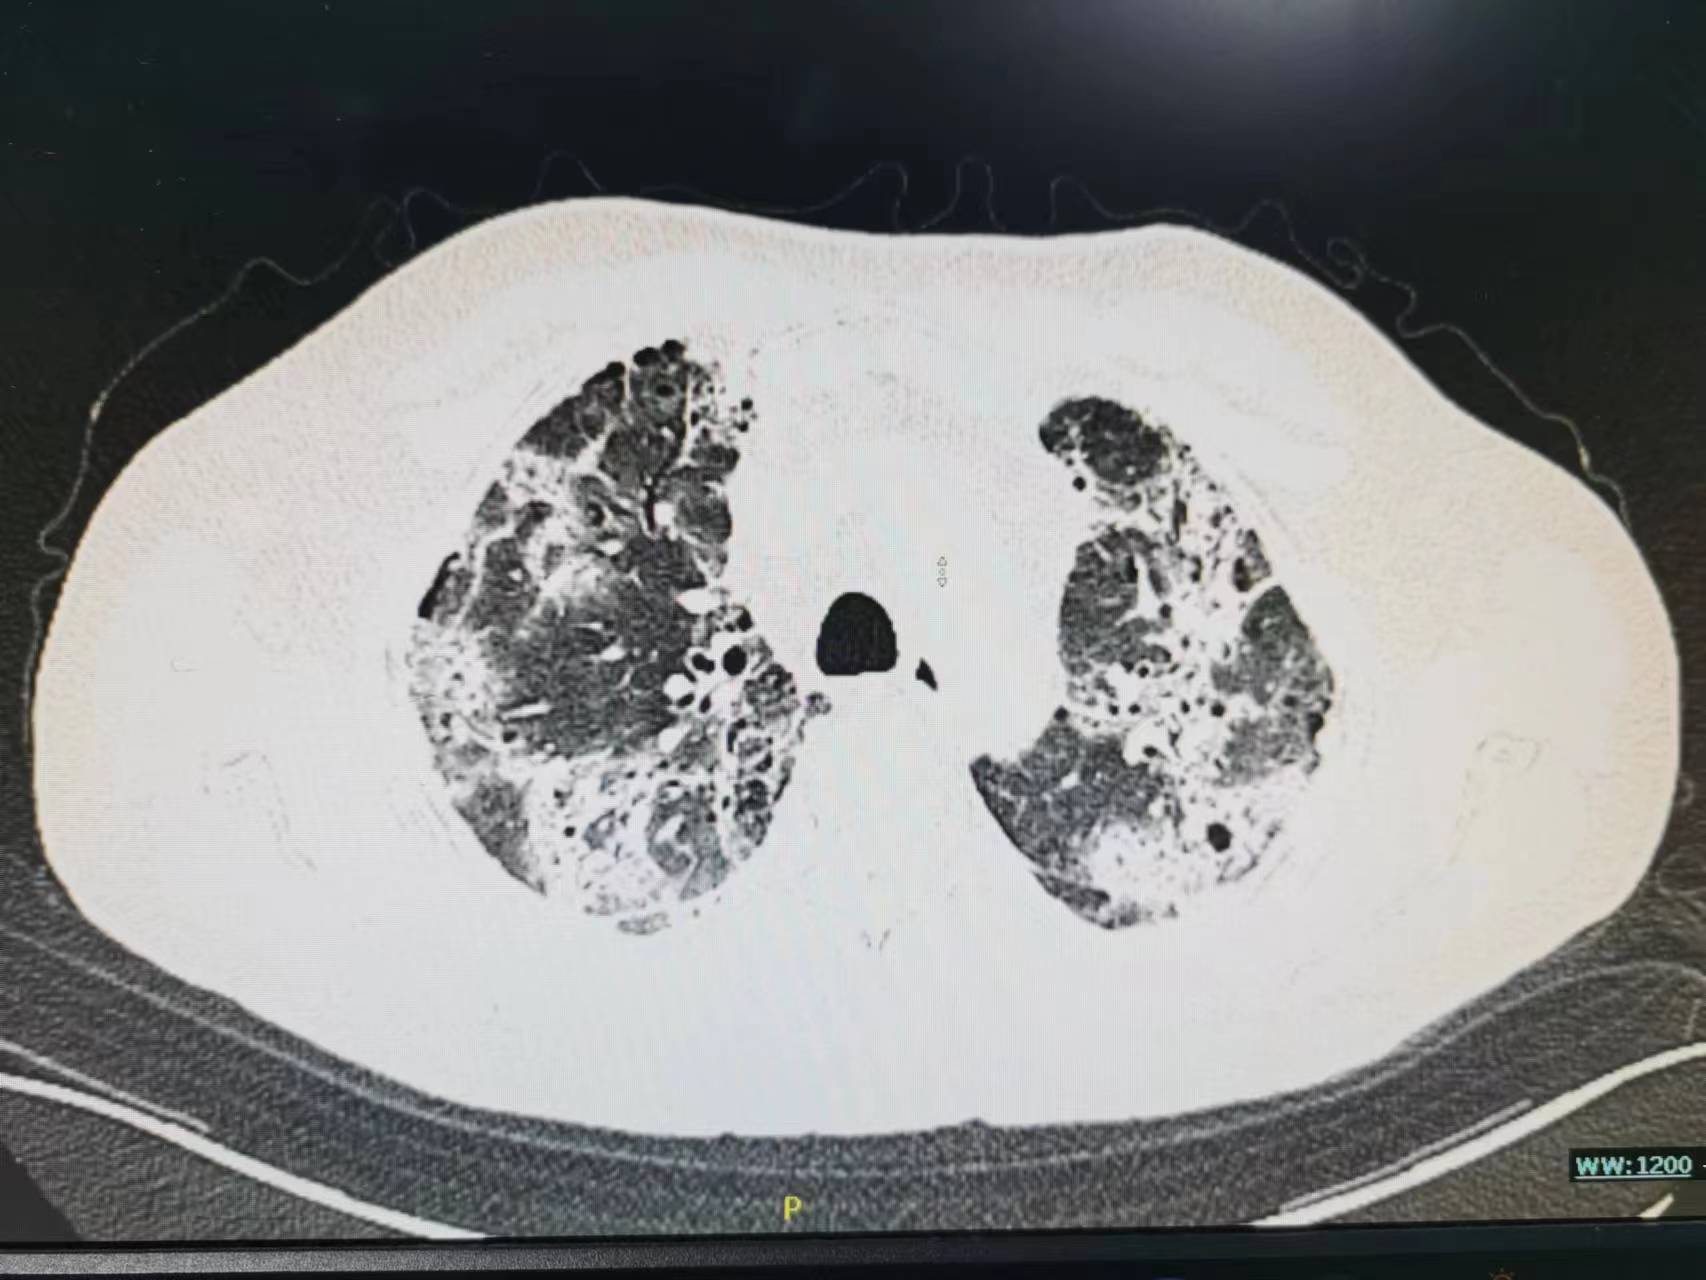

开始家属接受不了,找关系送老太太来医院是为了打“点滴”的,你给我说这个合适吗?病人的情况真有这么重吗?现在老太太不是好好的吗?于是再次向家属讲解病情,重点讲述了病人病情可能的发展并告知可能需要呼吸机,家属还是觉的不可能,查了胸部CT之后才发现病情已如此严重了,基本白肺了。这时候老太太才说这几天感觉到有点“憋的慌”,只是限于不想麻烦孩子的关系不想说,觉的忍忍就过去了。最后还是拗不过家属的要求才来医院的。

老年人阳后长期低热,肺部感染